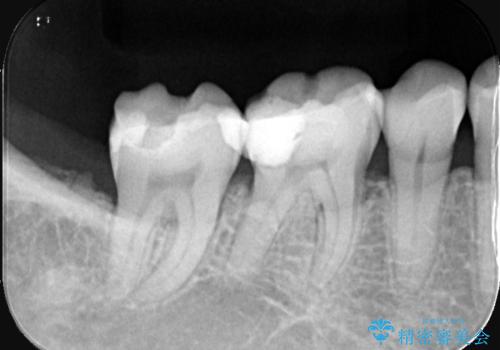

- 右下6番・7番の審美性と機能性を改善するため、セラミッククラウンでの治療を計画しました。1回目の来院時に古い被せ物や虫歯を丁寧に除去し、土台を整えた後に精密な型取りを行います。2回目の来院で仮のセラミッククラウンを装着して噛み合わせや適合性を確認し、最終調整を行います。3回目の来院時に完成したセラミッククラウンを装着し、最終調整を経て治療を完了します。

右下の奥歯にあった古い金属製のクラウンは、見た目の問題や歯ぐきの変色、さらには歯との境目に汚れが溜まりやすいなどの課題がありました。今回は審美的に優れ、生体親和性が高いセラミック素材を使用してクラウンを製作。色調は患者様の天然歯に合わせて調整を行い、自然で違和感のない仕上がりを目指しました。さらに精密な型取りと高度な技工技術を駆使することで、適合精度が非常に高いクラウンを提供しています。治療後は、見た目の美しさと噛み合わせの快適さが向上し、患者様には大変満足いただけました。